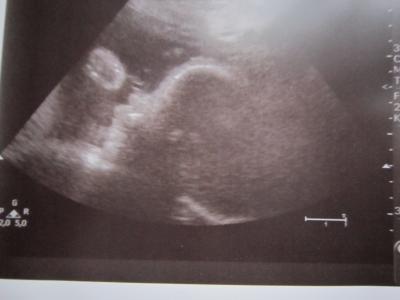

Halli,hallo zusammen.. So heute war es mal wieder soweit VU mit 3.Screening. Erstmal kam ich ans CTG die Maus schlief noch aber es dauerte nicht lange war ramba zamba angesagt. Ich muss da ja immer schmunzeln. Unsere erste Tochter hat immer brav geschlafen. CTG soweit ok 1. Wehe war zu sehen. Dann kam die Untersuchung MuMu und GMH alles bestens. Dann hat mich die Ärztin super gelobt wegen meinem Gewicht hab ja bis jetzt immer nur abgenommen und in den letzten 2 Wochen 500gr zugenommen und sie ist da richtig stolz auf mich. Mensch ich bin gleich 10cm gewachsen. Habe die SS Diabetis mit Ernährung im Griff und der Blutdruck ist auch top. So dann ab zum US. Als erstes wurde die Ärztin von unserer Maus getreten so das wir beide erstmal lachen mussten. Dann hat sie alles vermessen und doppler gemacht. Alles bestens sie ist höchst zufrieden. Unsere Maus ist nun ca. 42cm groß und 1950gr.schwer. Laut Daten wäre ich wohl etwas mehr als ne Woche weiter. Dann habe wir noch ein schönes 2D Bild hinbekommen,Profil mit geballter faust,sie fängt schn früh an.lach (hängt mit dran). Dann hat die Ärztin von sich aus 3D angemacht, was sie eigentlich nie macht und was macht unsere Maus nimmt beide Hände vor Gesicht und es wurde nix drauss mit einem schönen Foto, mensch hab ich mich geärgert,grins.. Nun darf ich jede Woche zum CTG und alle 2 Wochen zur VU. Magnesium soll ich bei 750mg bleiben und ich soll noch mehr trinken.. Oh man dieser Regen nervt mich heute total. Das will garnicht mehr aufhören,grrr..Gleich muss ich wieder los meine große"kleine" aus dem KiGa holen.. Wünsche euch allen noch einen schönen Tag. Passt schön auf euch auf.. LG Netti

Bild zu Zurück von VU und 3.Screening - Forum für Februar - Mamis